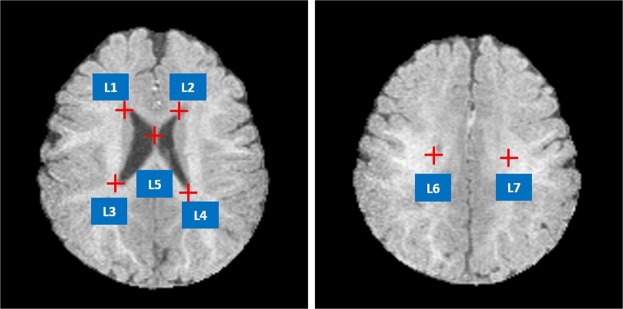

Iseg2017 and MRBrain13 datasets provide ground truth segmentation labels. Seven well-defined anatomic landmarks (see Fig. 6) that are distributed in the lateral ventricle are manually annotated by three doctors. We consider the average coordinates from three doctors as the ground truth positions of the landmarks.

Figure 6.

Illustration of the seven landmarks selected for cross-modality registration. L1: right lateral ventricle superior, L2: left lateral ventricle superior, L3: right lateral ventricle inferior, L4: left lateral ventricle inferior. L5: middle of the lateral ventricle, L6: right lateral ventricle posterior, L7: left lateral ventricle posterior.